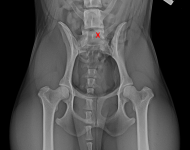

(3) 7 měsíců VD 1

(3) 7 měsíců VD 1

(3) typ 3 po korekci polohy pánve

(3) typ 3 po korekci polohy pánve

(4) 7 měsíců VD 2

(4) 7 měsíců VD 2

(4) typ 3 po korekci polohy pánve 2

(4) typ 3 po korekci polohy pánve 2